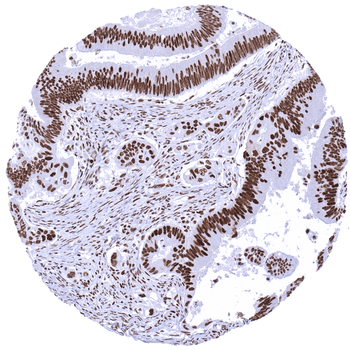

Colon Colorectal adenocarcinoma with strong MSH2 immunostaining in cancer cells and in stromal cells.